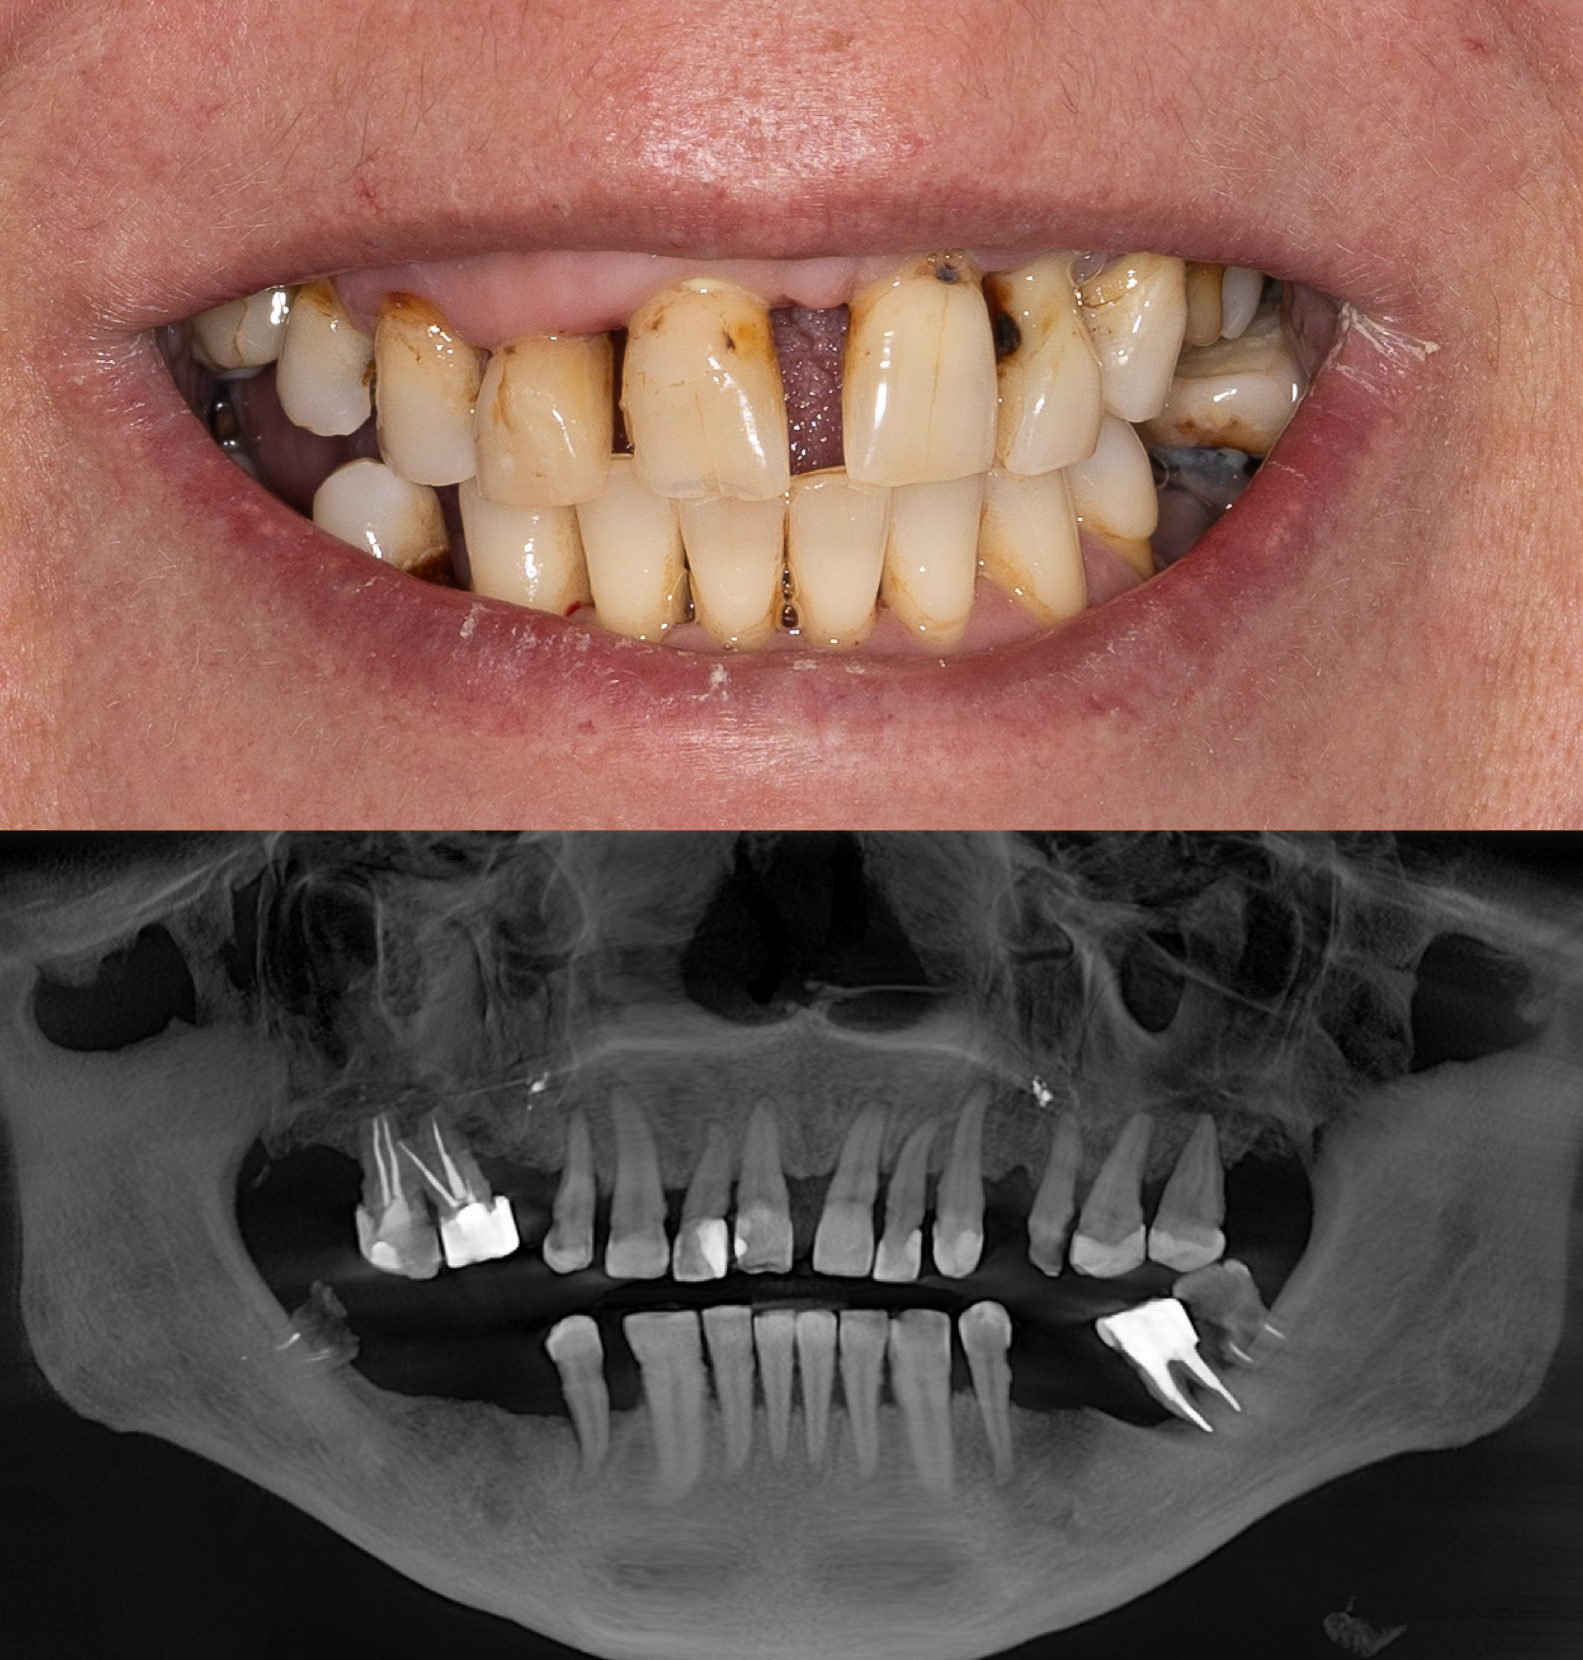

Pacjent zgłosił się z powodu licznych problemów z zębami oraz dolegliwości bólowych głowy. Zęby z powodu znacznej ruchomości nie stanowiły odpowiedniej podpory podczas żucia. Niestety wieloletniej terapia periodontologiczna choroby przyzębia nie przynosiła efektów. Zęby zostały zakwalifikowane do usunięcia. Nowy zgryz został odtworzony i oparty na 6 implantach w szczęce oraz 5 w żuchwie. Informacje z badania stawowe "kondylografii" pomogły zaplanować nowe prawidłowe zwarcie. Poza wyleczeniem dolegliwośći bólowych głowy oraz przywróceniu komfortu żucia i uśmiechu, Pacjent po zakończonej terapii zgłasza znaczne ograniczenie chrapania.

leczenie zaplanował oraz przeprowadził lek. dent Kamil Kikowicz